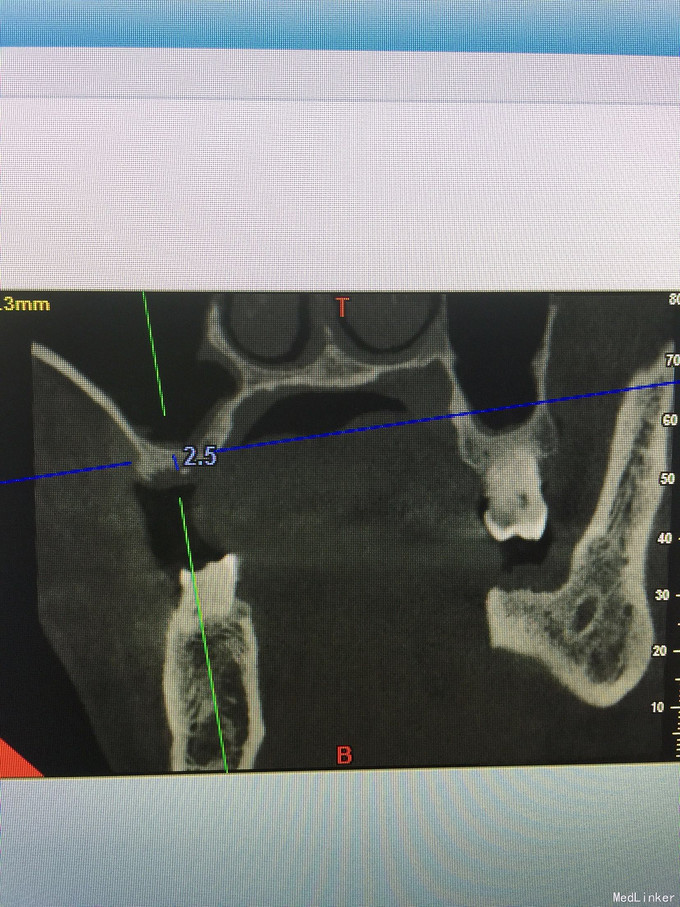

张先生,右上6缺失多年,要求种植

骨量只有2.4毫米

上颌窦内提,同期植入4.1-10植体